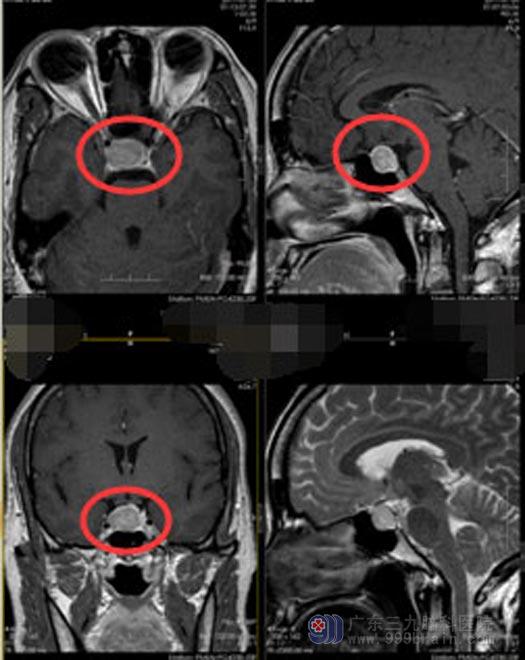

李女士几个月前开始头痛头晕,在附近医院检查后,诊断为“颅内鞍区占位--考虑垂体大腺瘤”。由于当地医院的技术和设备难以满足李女士治疗需求,她来到了广东三九脑科医院的神经外五科。

▲手术前

垂体腺瘤起源于蝶鞍内的垂体,其周围结构复杂,有正常的垂体、颈内动脉、海绵窦、多个颅神经、视交叉、下丘脑等重要结构包绕或比邻,手术中的任何偏差都有可能引起严重后果。